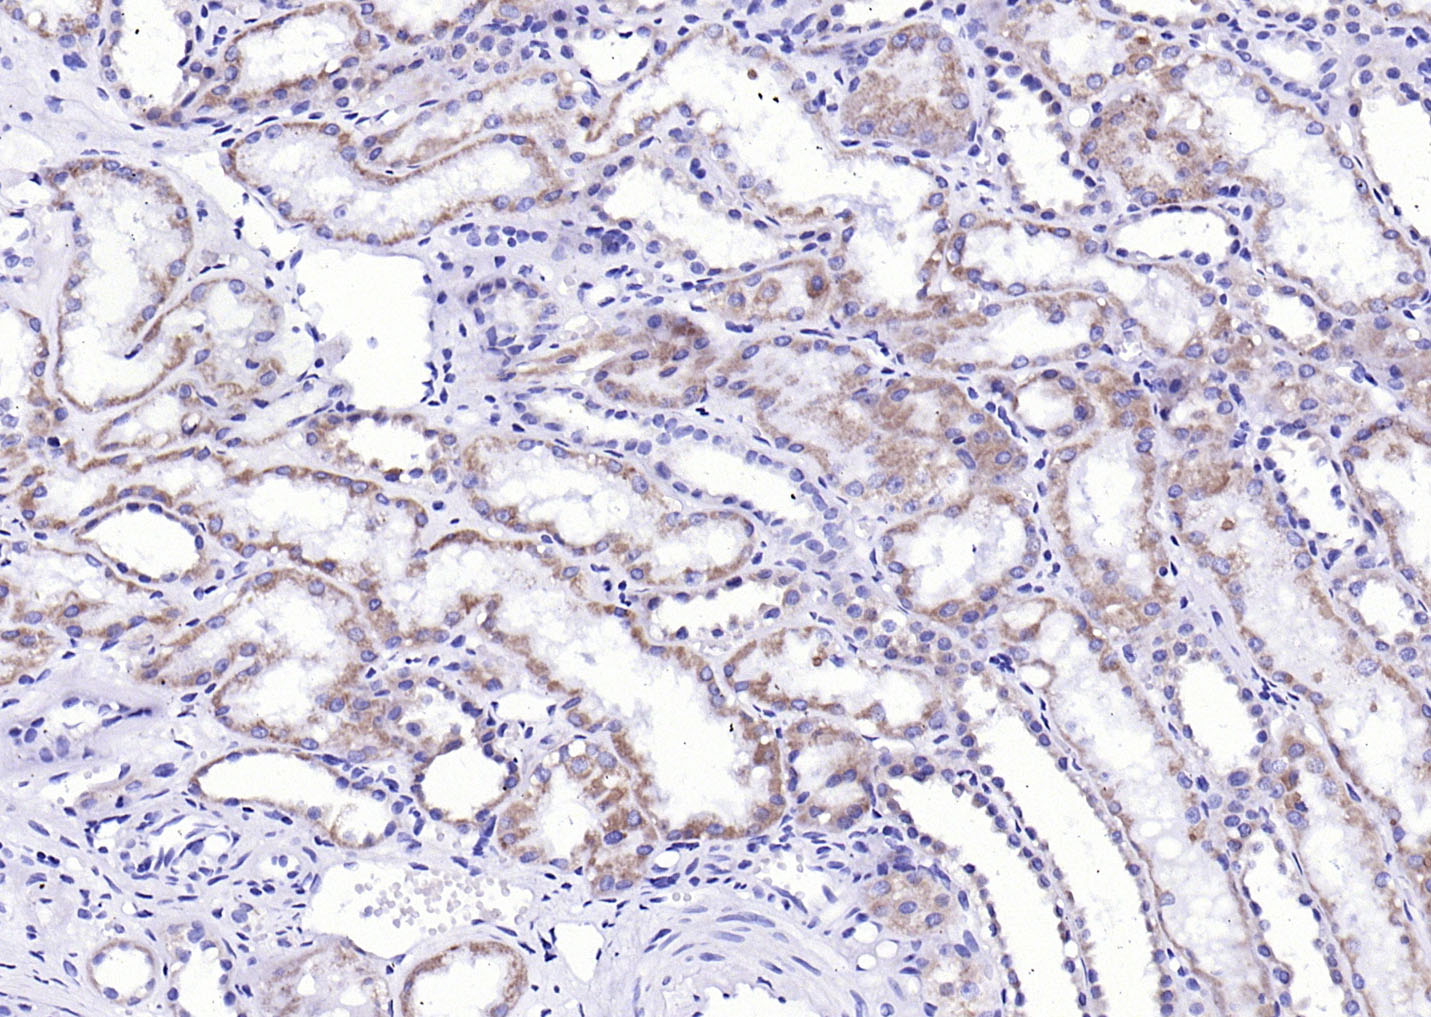

Paraformaldehyde-fixed, paraffin embedded (Human kidney); Antigen retrieval by boiling in sodium citrate buffer (pH6.0) for 15min; Block endogenous peroxidase by 3% hydrogen peroxide for 20 minutes; Blocking buffer (normal goat serum) at 37°C for 30min; Antibody incubation with (LPA1) Polyclonal Antibody, Unconjugated (bs-22137R) at 1:200 overnight at 4°C, followed by operating according to SP Kit(Rabbit) (sp-0023) instructionsand DAB staining.